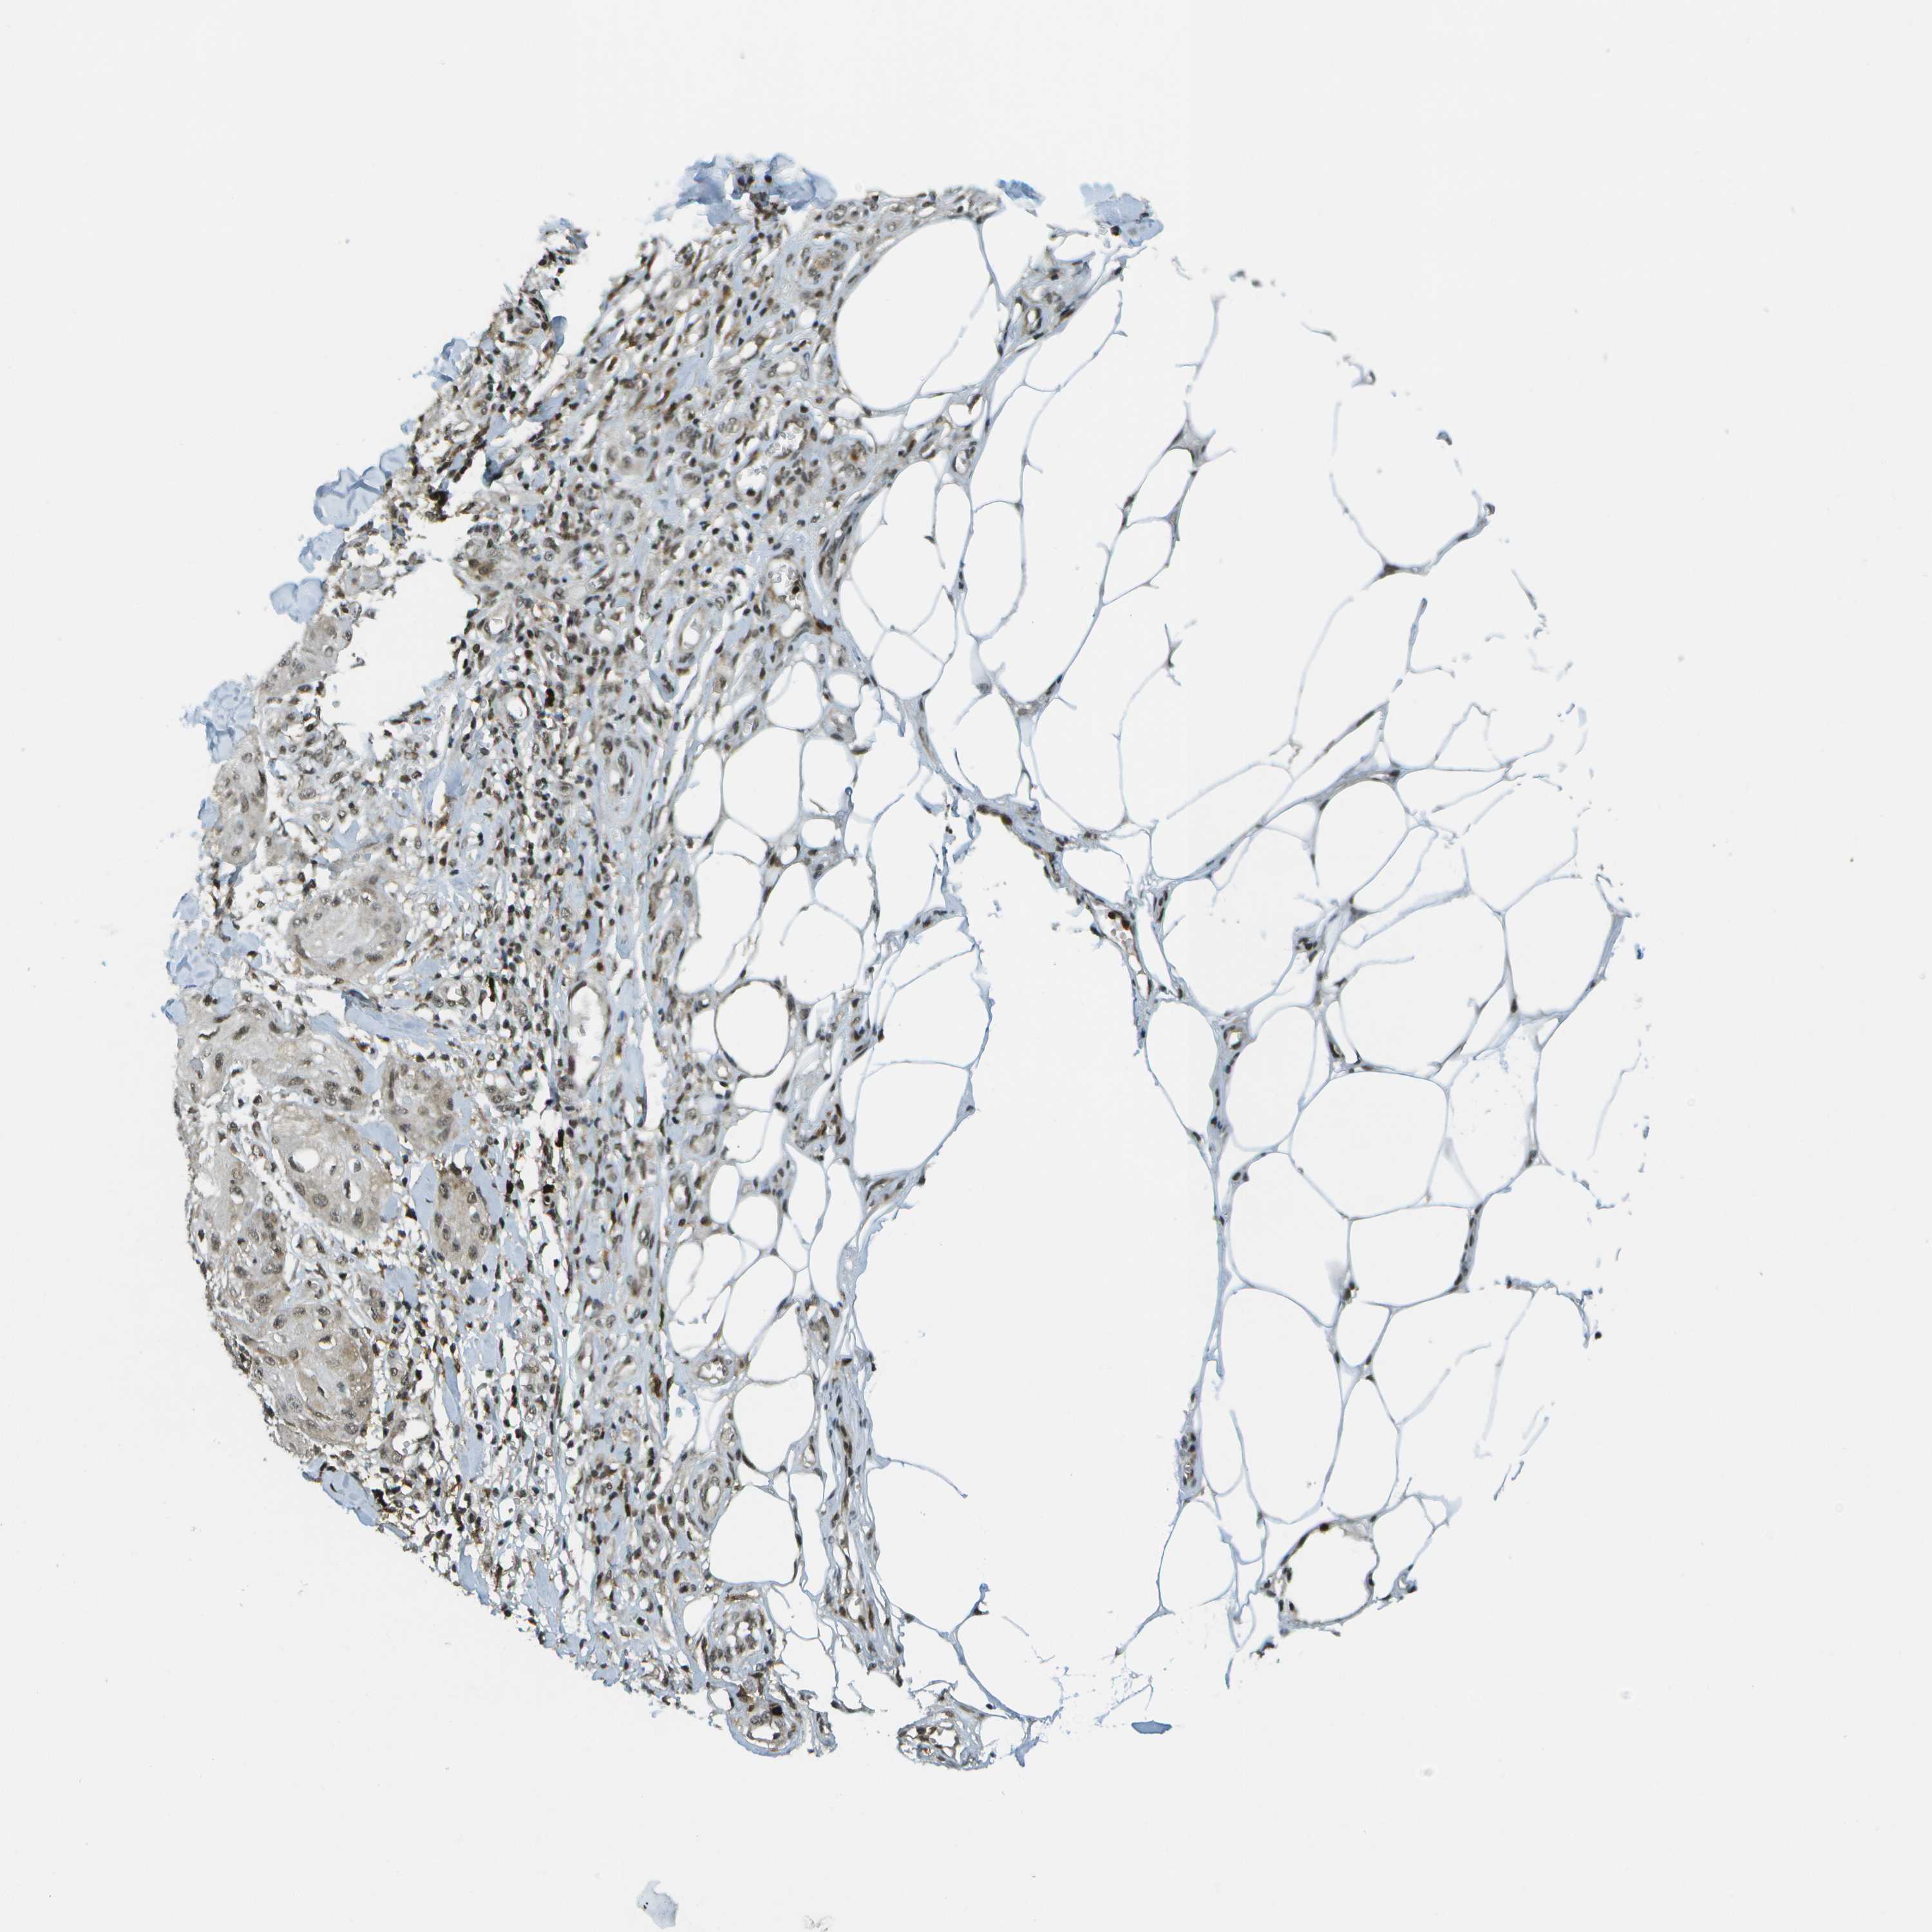

SKIN CANCER - Protein expressioni

A mouse-over function shows sample information and annotation data. Click on an image to view it in a full screen mode. Samples can be filtered based on level of antibody staining by selecting one or several of the following categories: high, medium, low and not detected. The assay and annotation is described here.

Antibody stainingi

Antibody staining in the annotated cell types in the current human tissue is reported as not detected, low, medium, or high, based on conventional immunohistochemistry profiling in selected tissues. This score is based on the combination of the staining intensity and fraction of stained cells.

Each image is clickable and will lead to virtual microscopy that enables deeper exploration of all samples and also displays staining intensity scores, fraction scores and subcellular localization as well as patient and tissue information for each sample.

Antibody CAB017694

Basal cell carcinoma

Adnexal tumor, benign